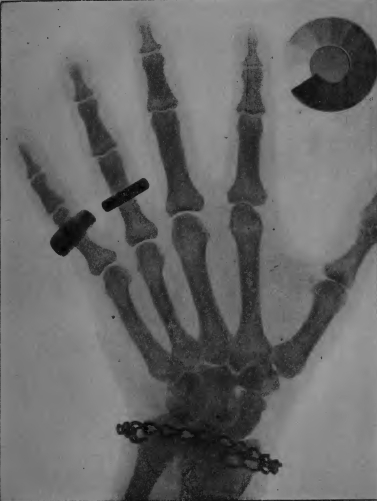

Planche II. — Radiographie d'une main (positif). A l'annulaire une bague d'or très opaque aux rayons X. Au petit doigt une bague d'aluminium bien moins opaque: l'ombre de l'os s'aperçoit au travers de cette bague. Au poignet un bracelet de fer avec une plaque d'aluminium mince, peu visible sur la radiographie en raison de sa transparence. Les os, bien moins opaques que les bagues, donnent cependant des ombres très nettes laissant voir des détails de structure. Le contour des chairs se voit faiblement. A côté de la main se trouve un radiochromomètre radiographié en même temps que celle-ci. Il indique une dureté de rayons de 6e Benoist.